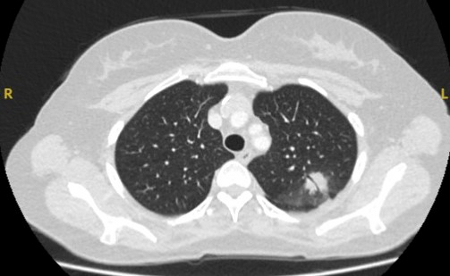

Nódulos sólidos: um tempo de duplicação do volume >600 dias não requer acompanhamento, enquanto um tempo de duplicação do volume <400 dias, ou crescimento nítido definido como um aumento de 25% ou mais no volume, sugere a necessidade de investigações diagnósticas.[Figure caption and citation for the preceding image starts]: Tomografia computadorizada (TC) mostrando nódulo solitário espiculado no lobo superior direito dentro de enfisema, em fumante atual com exposição prévia ao amianto. Observe a placa pleural visível no lado esquerdo. A histologia da ressecção revelou adenocarcinoma do pulmãoDo acervo de Dr. George Tsaknis, MD, PhD, FRCP (Londres), MRQA, MAcadMEd, PGCert; usado com permissão [Citation ends].